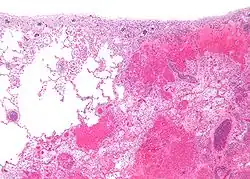

Micrograph of testis showing hemorrhagic infarction. H&E stain.